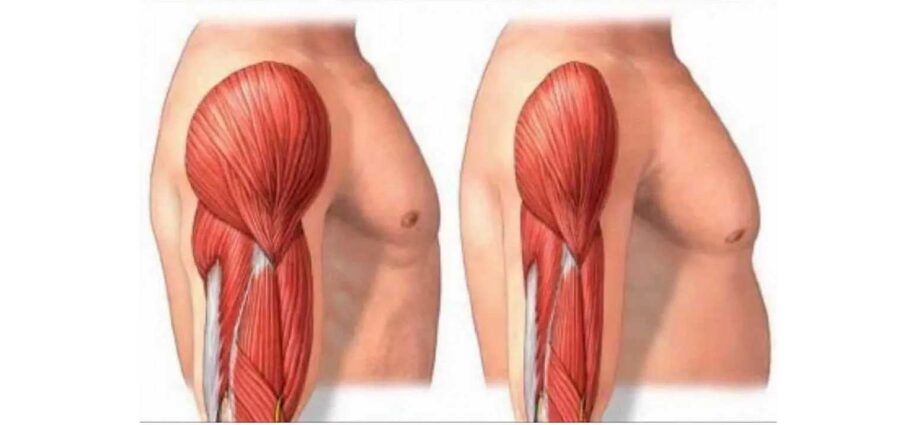

Pratiquement tous les organes, tous les tissus et toutes les cellules sont soumis à ce renouvellement cellulaire permanent et vont être complètement régénérés plusieurs fois dans une vie, à une fréquence plus ou moins élevée en fonction des cellules. Ce qui fait qu’au bout du compte, l’immense majorité des cellules et des organes sont plus jeunes que l’individu lui-même.

Ce vaste écosystème cellulaire – qui est finalement notre organisme – contient environ 250 types de cellules différentes. La grande majorité est soumise au renouvellement cellulaire, sauf quelques exceptions, comme, par exemple, les neurones et les cellules cardiaques où le renouvellement est très lent ou quasi inexistant.